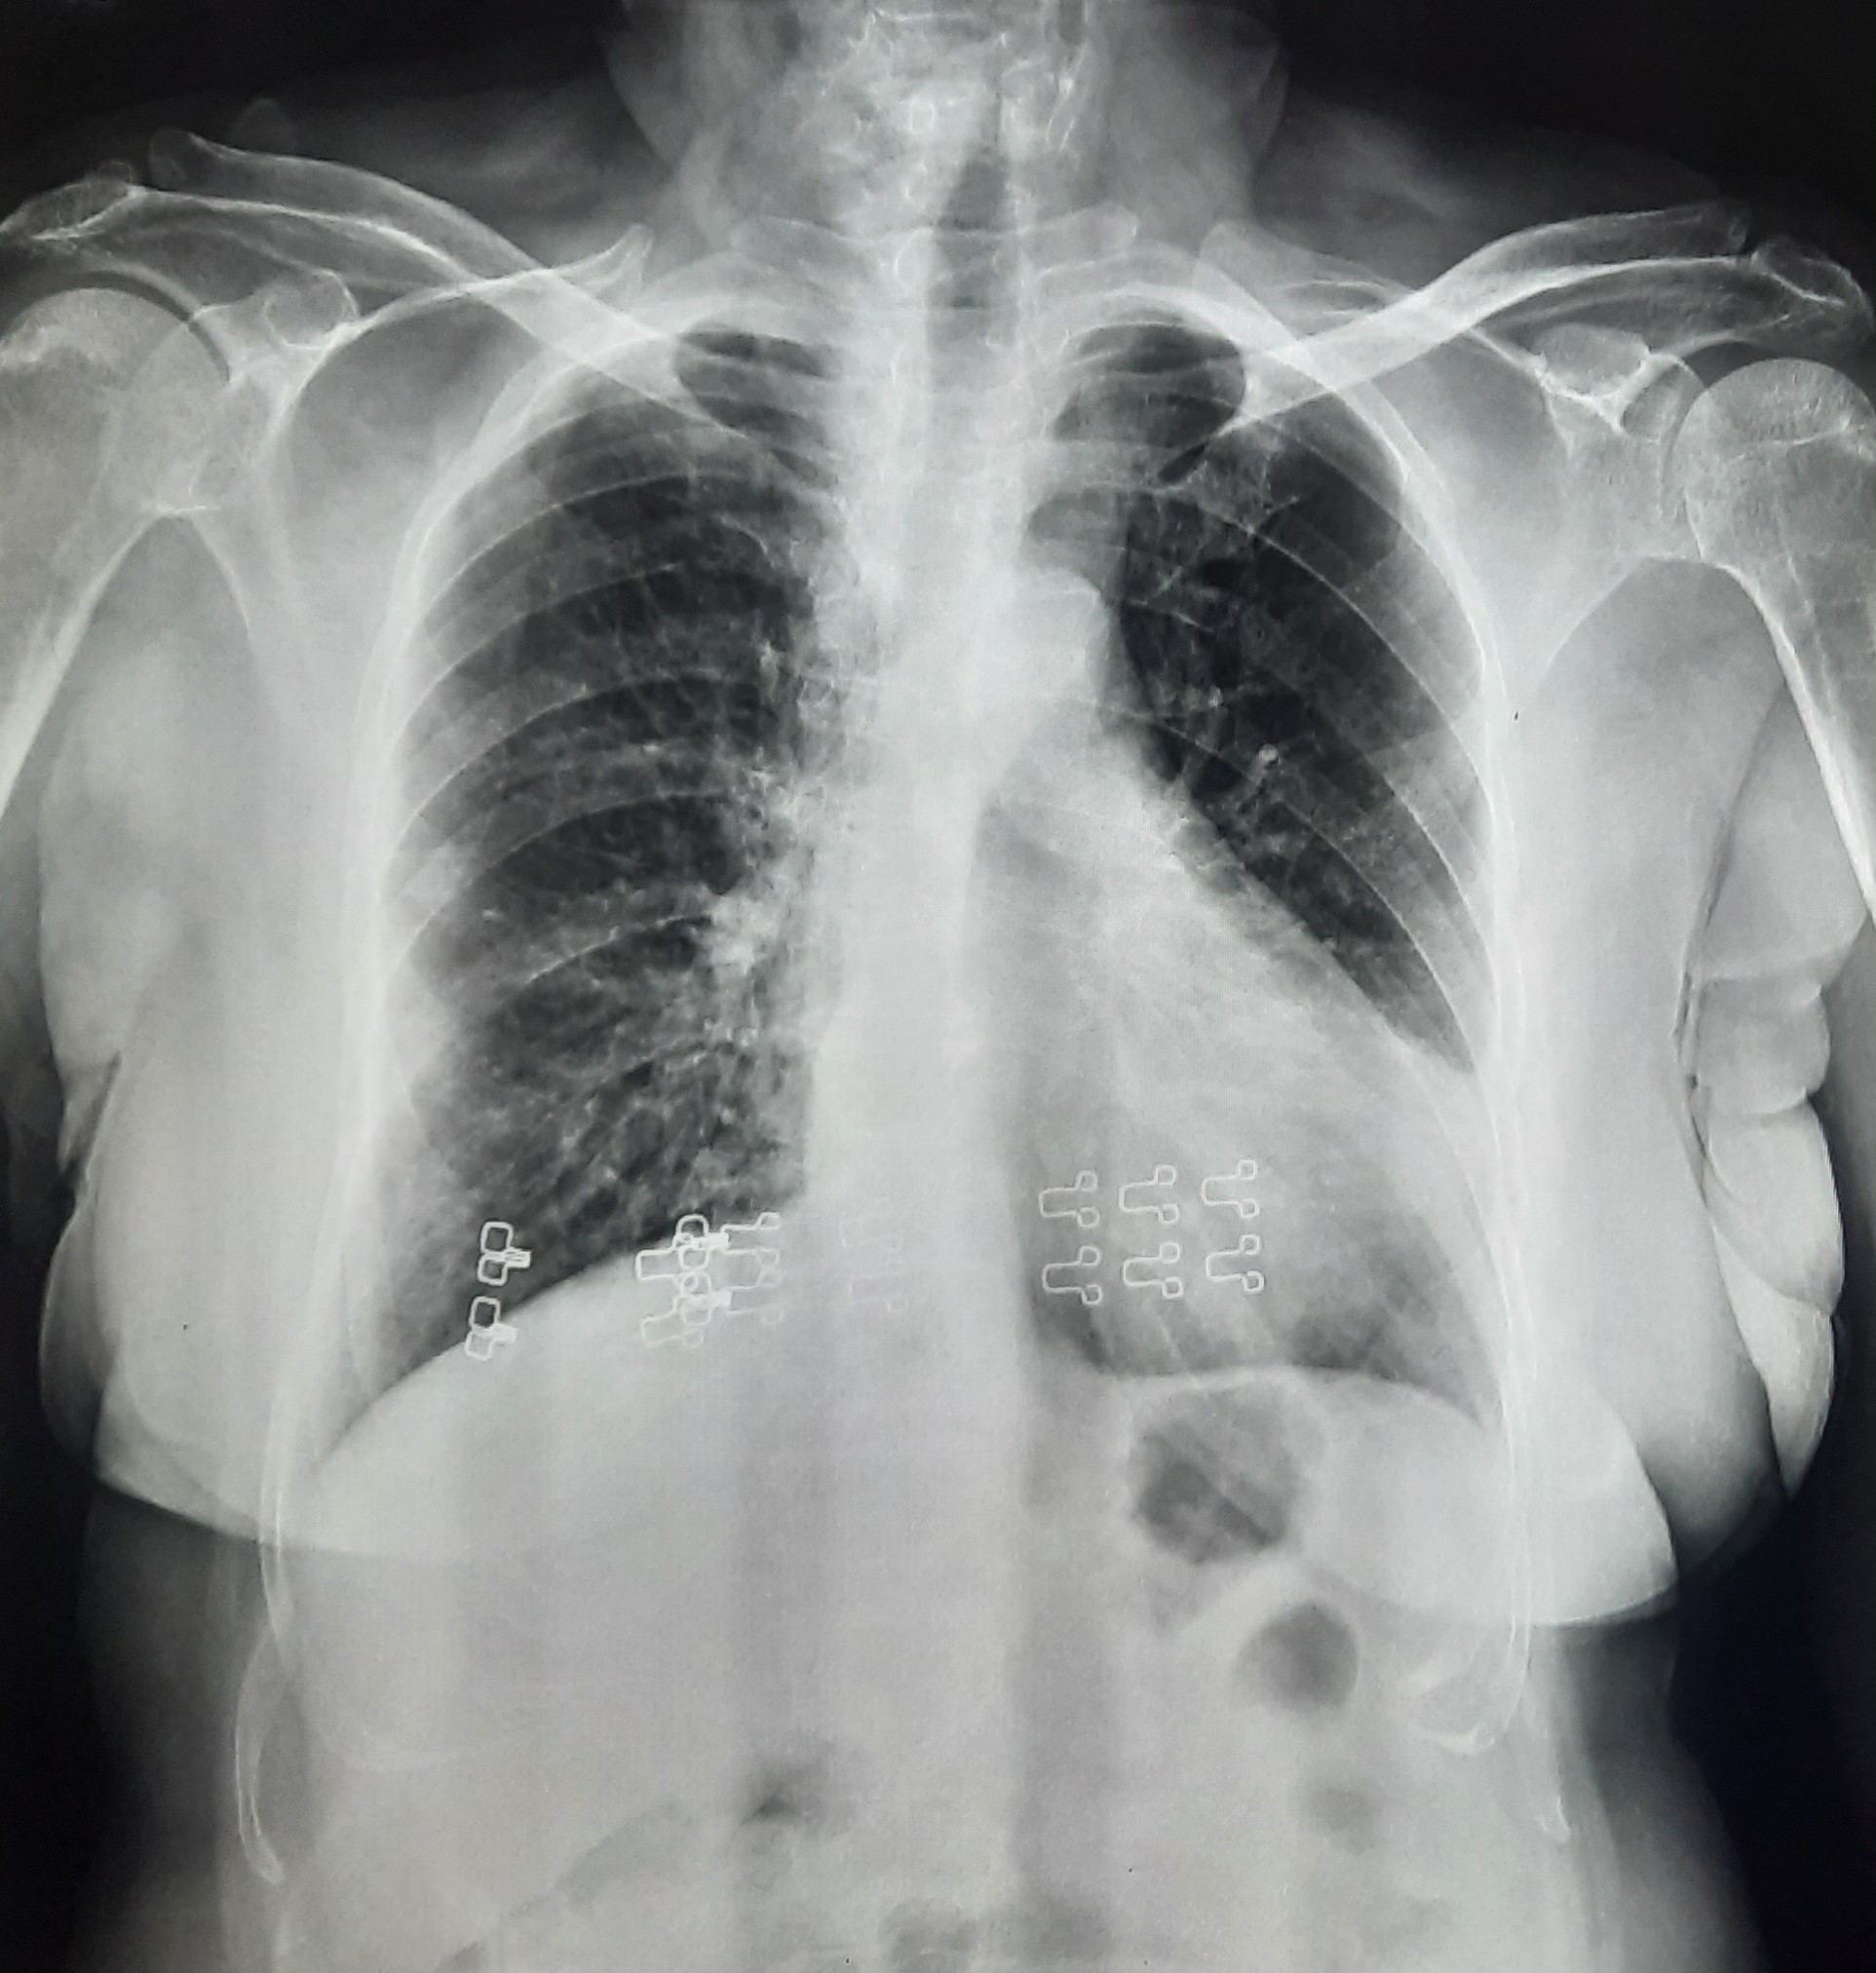

| 60 | IGGMC, Nagpur, Nagpur | P2 | 29-4412 | Ritesh Uikey | Consent taken on Paper | 30 Yrs. |

Provisional Diag : Pulmonary Tuberculosis

Final Diag : Pulmonary Tuberculosis |

TB Case (Confirmed) | Bilateral Lung Infiltration Present & Right Upper Zone Cavity Present | Abnormality visible on x-ray |